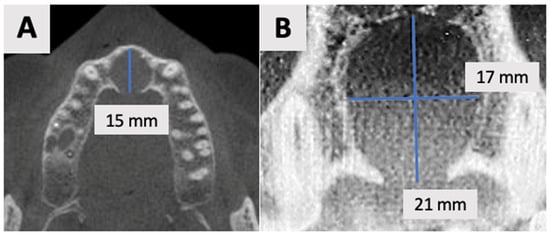

Cone Beam Computed Tomography (CBCT) was performed using the NewTom GO 2D/3D® system (NewTom, Verona, Italy). Imaging was performed to assess the extent and characteristics of the lesion (Figure 1). The CBCT revealed a unilocular hypodense area palatal to the anterior four maxillary teeth, absence of palatal bony walls and intact buccal bony frame. Lesion dimensions were 17 mm (mesiodistal) × 15 mm (buccolingual) × 21 mm (height). These radiographic findings are consistent with the characteristics of a radicular cyst, which typically presents as a well-defined, unilocular radiolucency associated with the apex of a non-vital tooth. The absence of palatal bony walls suggests potential expansion or erosion of the palatal cortex.

Figure 1.

Radiographic images of the cyst at initial visit before marsupialization. (A) Axial, and (B) coronal views of the cyst center. Measurements indicate cyst dimensions: mesiodistal 17 mm × buccolingual 15 mm × height 21 mm.